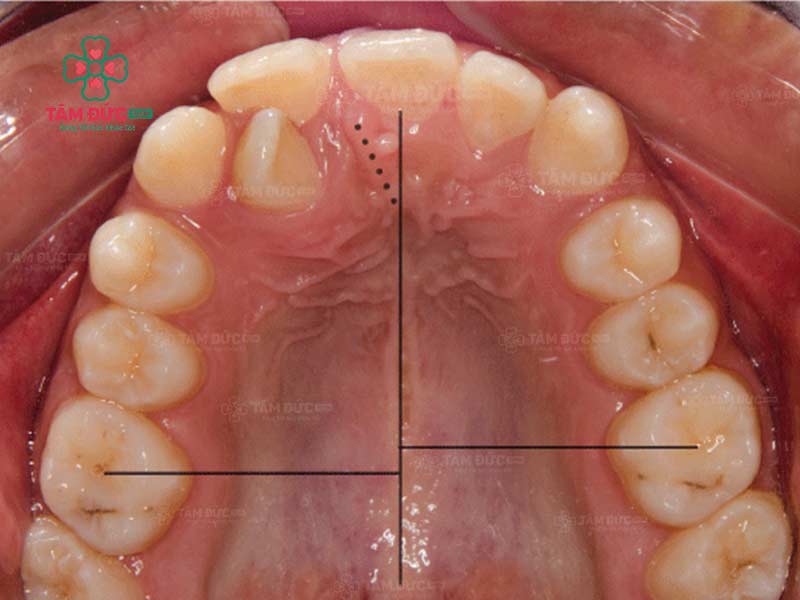

răng lệch nhân trung

Trường hợp bị lệch nhân trung